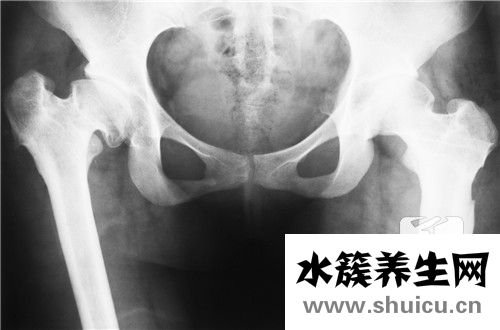

髖關(guān)節(jié)滑膜炎是一種不治之癥,由先天性髖關(guān)節(jié)發(fā)育不良引起,會(huì)導(dǎo)致骨骼畸形,進(jìn)而導(dǎo)致嬰兒骨盆發(fā)育不良和髖關(guān)節(jié)疼痛。需要孩子環(huán)節(jié)的物理糾正,錯(cuò)過了最好的時(shí)間也無法治愈。根據(jù)兒童髖關(guān)節(jié)滑膜炎的病因,可以掌握以下幾點(diǎn),做好適當(dāng)?shù)闹委煛?/p>

最先,先天的髖關(guān)滑膜炎,便是一種小寶寶的髖關(guān)位置發(fā)育不全的病癥,是很廣泛的嬰兒階段四肢產(chǎn)生畸型的一種病癥,是不可以治愈的。因?yàn)橄忍斓捏y關(guān)滑膜炎與因創(chuàng)傷導(dǎo)致的發(fā)炎,是有較為大的差別。得了先天的髖關(guān)滑膜炎的小寶寶實(shí)際上不容易感覺有痛感,對(duì)于蹲下、站立起來這種姿勢(shì)也都沒一切艱難。

次之,小嬰兒出生后的第一年盆骨層面的生長(zhǎng)發(fā)育非常快速,伴隨著小寶寶的漸漸地發(fā)展,盆骨生長(zhǎng)發(fā)育基本定形之后便會(huì)越來越較為無法治療了。而有一部分本性的髖關(guān)滑膜炎的小寶寶剛好便是由于發(fā)覺的較為晚了,因而就錯(cuò)過能夠 做物理學(xué)性層面對(duì)策開展糾正,只有根據(jù)接納手術(shù)治療的復(fù)位醫(yī)治。所以說,得了髖關(guān)滑膜炎一定要引起重視。